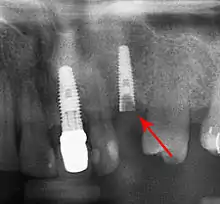

Bone loss (peri-implantitis) on implants over 7 years in a heavy smoker

Fixture show

Recession of the gingiva leads to exposure of the metal abutment under a dental crown.

Fracture of abutment screws (arrow) in 3 implants required removal of the remainder of the screw and replacement.

Cement peri-implantitis

Dental cement under the gingiva causes peri-implantitis and implant failure.